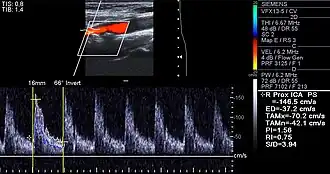

Doppler ultrasound of right internal carotid artery with calcified and non-calcified plaques showing less than 70% stenosis

Lumen stenosis that is greater than 75% was considered the hallmark of clinically significant disease in the past because recurring episodes of angina and abnormalities in stress tests are only detectable at that particular severity of stenosis. However, clinical trials have shown that only about 14% of clinically debilitating events occur at sites with more than 75% stenosis. Most cardiovascular events that involve the sudden rupture of the atheroma plaque do not display any evident luminal narrowing. Thus, greater attention has been focused on "vulnerable plaque" since the late 1990s.[84]

Examples of anatomical detection methods include coronary calcium scoring by CT, carotid IMT (intimal media thickness) measurement by ultrasound, and intravascular imaging techniques, such as intravascular ultrasound (IVUS), and intravascular optical coherence tomography (OCT),[85][86] allowing direct visualization of atherosclerotic plaques.